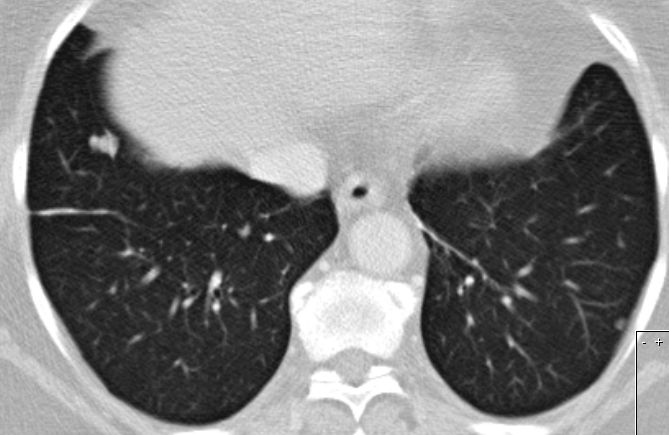

| Metastasierung | Lungenmetastasen und Lokalrezidiv 1 Jahr nach Leiomyosarkom der rechten Beckenwand.

![]() | ||